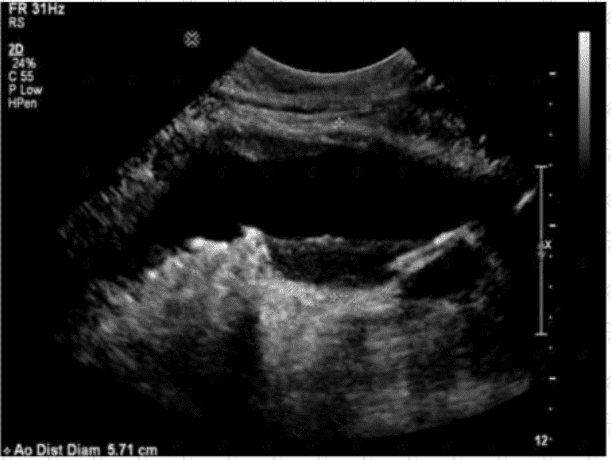

Which action should a sonographer take if the abdominal aorta measures 5.5 centimeters in the anteroposterior diameter?

Which sonographic finding is most consistent with this image of the abdominal aorta?